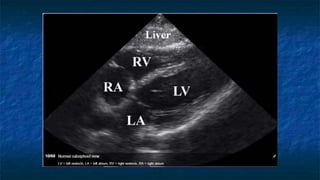

1) Subxiphoid exam

 Probe placed

 Transversally

 Midline plane

 Just below subxiphoid region

 Probe facing towards patient’s right

FAST: Subxiphoid exam

 Normal Anatomy

 Liver at very top of screen

 Epicardial fat vs. effusion

 Thin layer anterior to

RV

 Not present posterior

to LV

Normal Subxiphoid exam